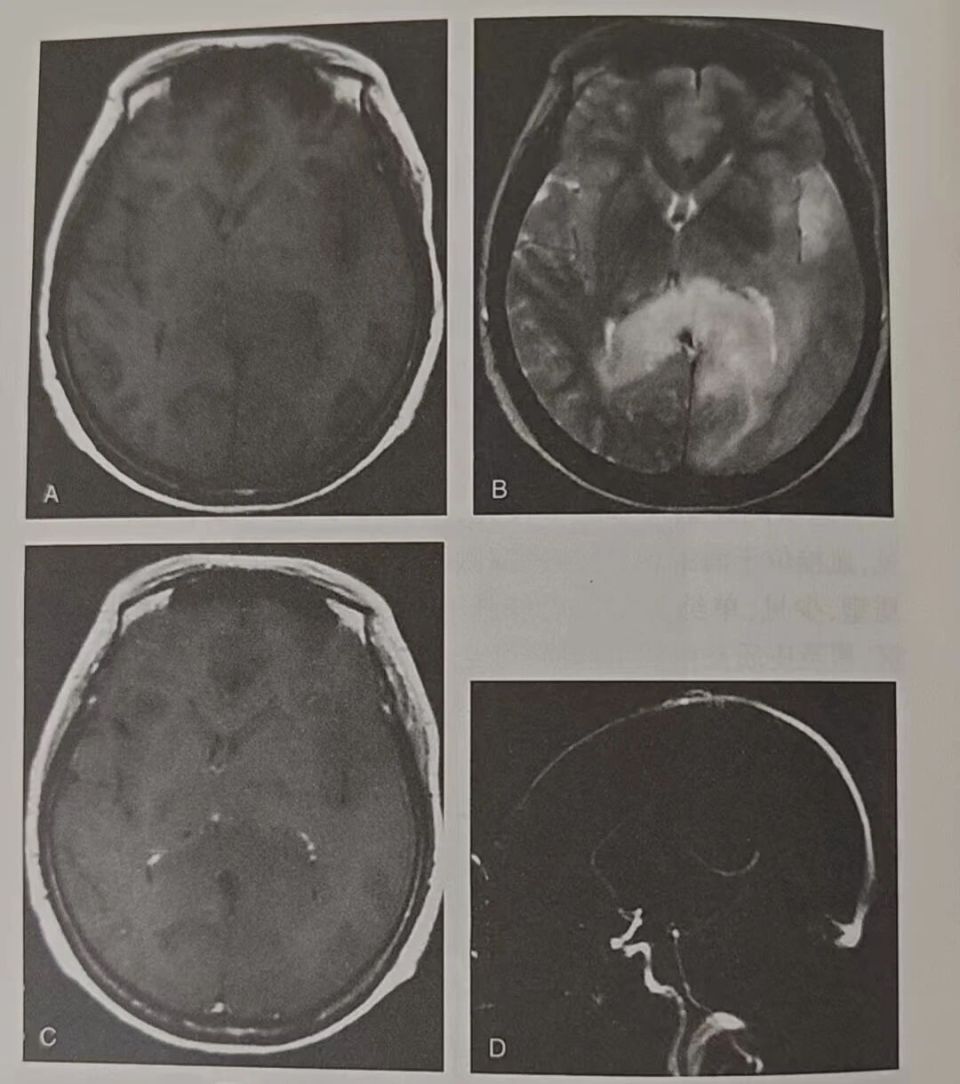

影像学上一般表现为静脉梗死区域脑肿胀(图4),T1WI呈稍低信号,T2WI呈高信号,病灶图像在T2FLAIR序列比DWI序列上范围更大,可伴灶性出血,约1/3的静脉性脑梗死表现为脑梗死后出血性转化。静脉性脑梗死所致脑水肿以血管源性水肿(DWI呈高信号,ADC呈高信号改变)为主,多可逆转;伴或不伴有细胞毒性水肿(DWI呈高信号,ADC呈低信号改变),不可逆转。增强扫描皮质静脉梗死可见脑回样强化,深部灰质核团、丘脑或脑干病变常为斑片状不规则强化。

图片

图4.多发静脉性脑梗死影像学表现

A.TWI示左侧颞枕叶及胼胝体压部脑组织肿胀,可见团片状低信号;B.T2WI上述区域呈高信号,病变肿胀,占位效应明显;C.注射对比剂后上述区域未见明显强化;D.TOF-MRV显示大脑大静脉及直窦明显变细,部分不连续,证实深静脉血栓所致静脉性脑梗死。